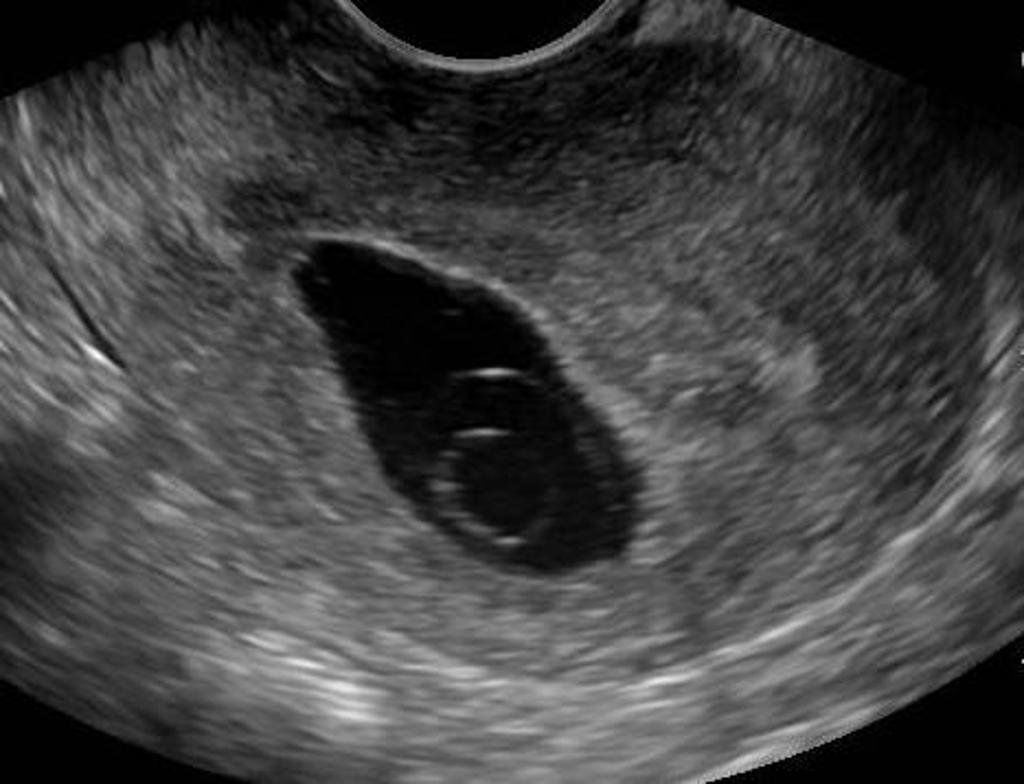

Thai 5 Tuần Chưa Có Phôi

Ảnh trên: Thai 5 Tuần Chưa Có Phôi

Thai 5 tuần chưa có phôi là một thuật ngữ y khoa mô tả kết quả siêu âm cho thấy túi thai (gestational sac) đã hiện diện trong buồng tử cung nhưng chưa ghi nhận được hình ảnh phôi thai (embryo) bên trong. Đây là một tình trạng tương đối phổ biến trong giai đoạn đầu của thai kỳ và cần được đánh giá cẩn thận.

Theo Hiệp hội Sản phụ khoa Hoa Kỳ (ACOG), tuổi thai 5 tuần được tính từ ngày đầu tiên của kỳ kinh cuối cùng. Ở thời điểm này, phôi thai, nếu phát triển bình thường, chỉ mới bắt đầu hình thành và có kích thước rất nhỏ, thường chỉ vài milimet. Do đó, việc quan sát phôi thai phụ thuộc rất nhiều vào độ phân giải của máy siêu âm và thời điểm thụ thai chính xác.

Tiêu chuẩn chẩn đoán thai 5 tuần trên siêu âm

Ở tuần thứ 5, siêu âm (thường là siêu âm đầu dò âm đạo) có thể phát hiện các cấu trúc sau:

– Túi thai (Gestational Sac): Đây là cấu trúc đầu tiên có thể nhìn thấy, xuất hiện dưới dạng một vòng tròn nhỏ, rỗng, màu đen bên trong nội mạc tử cung.

– Túi noãn hoàng (Yolk Sac): Thường xuất hiện sau túi thai, là một vòng tròn nhỏ, sáng bên trong túi thai, có vai trò cung cấp dinh dưỡng ban đầu cho phôi. Sự hiện diện của túi noãn hoàng thường là một dấu hiệu tích cực, xác nhận đây là một túi thai thật.

Việc chưa thấy phôi ở tuần thứ 5 có thể nằm trong giới hạn bình thường, đặc biệt khi phôi còn quá nhỏ hoặc chưa phát triển đến mức có thể quan sát được.